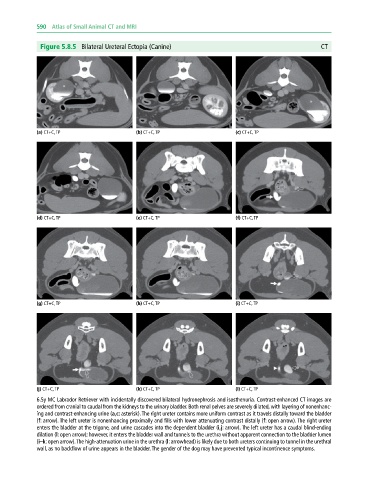

Figure 5.8.5 Bilateral Ureteral Ectopia (Canine) CT

(a) CT+C, TP (b) CT+C, TP (c) CT+C, TP

(d) CT+C, TP (e) CT+C, TP (f) CT+C, TP

(g) CT+C, TP (h) CT+C, TP (i) CT+C, TP

(j) CT+C, TP (k) CT+C, TP (l) CT+C, TP

6.5y MC Labrador Retriever with incidentally discovered bilateral hydronephrosis and isosthenuria. Contrast‐enhanced CT images are

ordered from cranial to caudal from the kidneys to the urinary bladder. Both renal pelves are severely dilated, with layering of nonenhanc-

ing and contrast‐enhancing urine (a,c: asterisk). The right ureter contains more uniform contrast as it travels distally toward the bladder

(f: arrow). The left ureter is nonenhancing proximally and fills with lower attenuating contrast distally (f: open arrow). The right ureter

enters the bladder at the trigone, and urine cascades into the dependent bladder (i,j: arrow). The left ureter has a caudal blind‐ending

dilation (l: open arrow); however, it enters the bladder wall and tunnels to the urethra without apparent connection to the bladder lumen

(i–k: open arrow). The high‐attenuation urine in the urethra (l: arrowhead) is likely due to both ureters continuing to tunnel in the urethral

wall, as no backflow of urine appears in the bladder. The gender of the dog may have prevented typical incontinence symptoms.